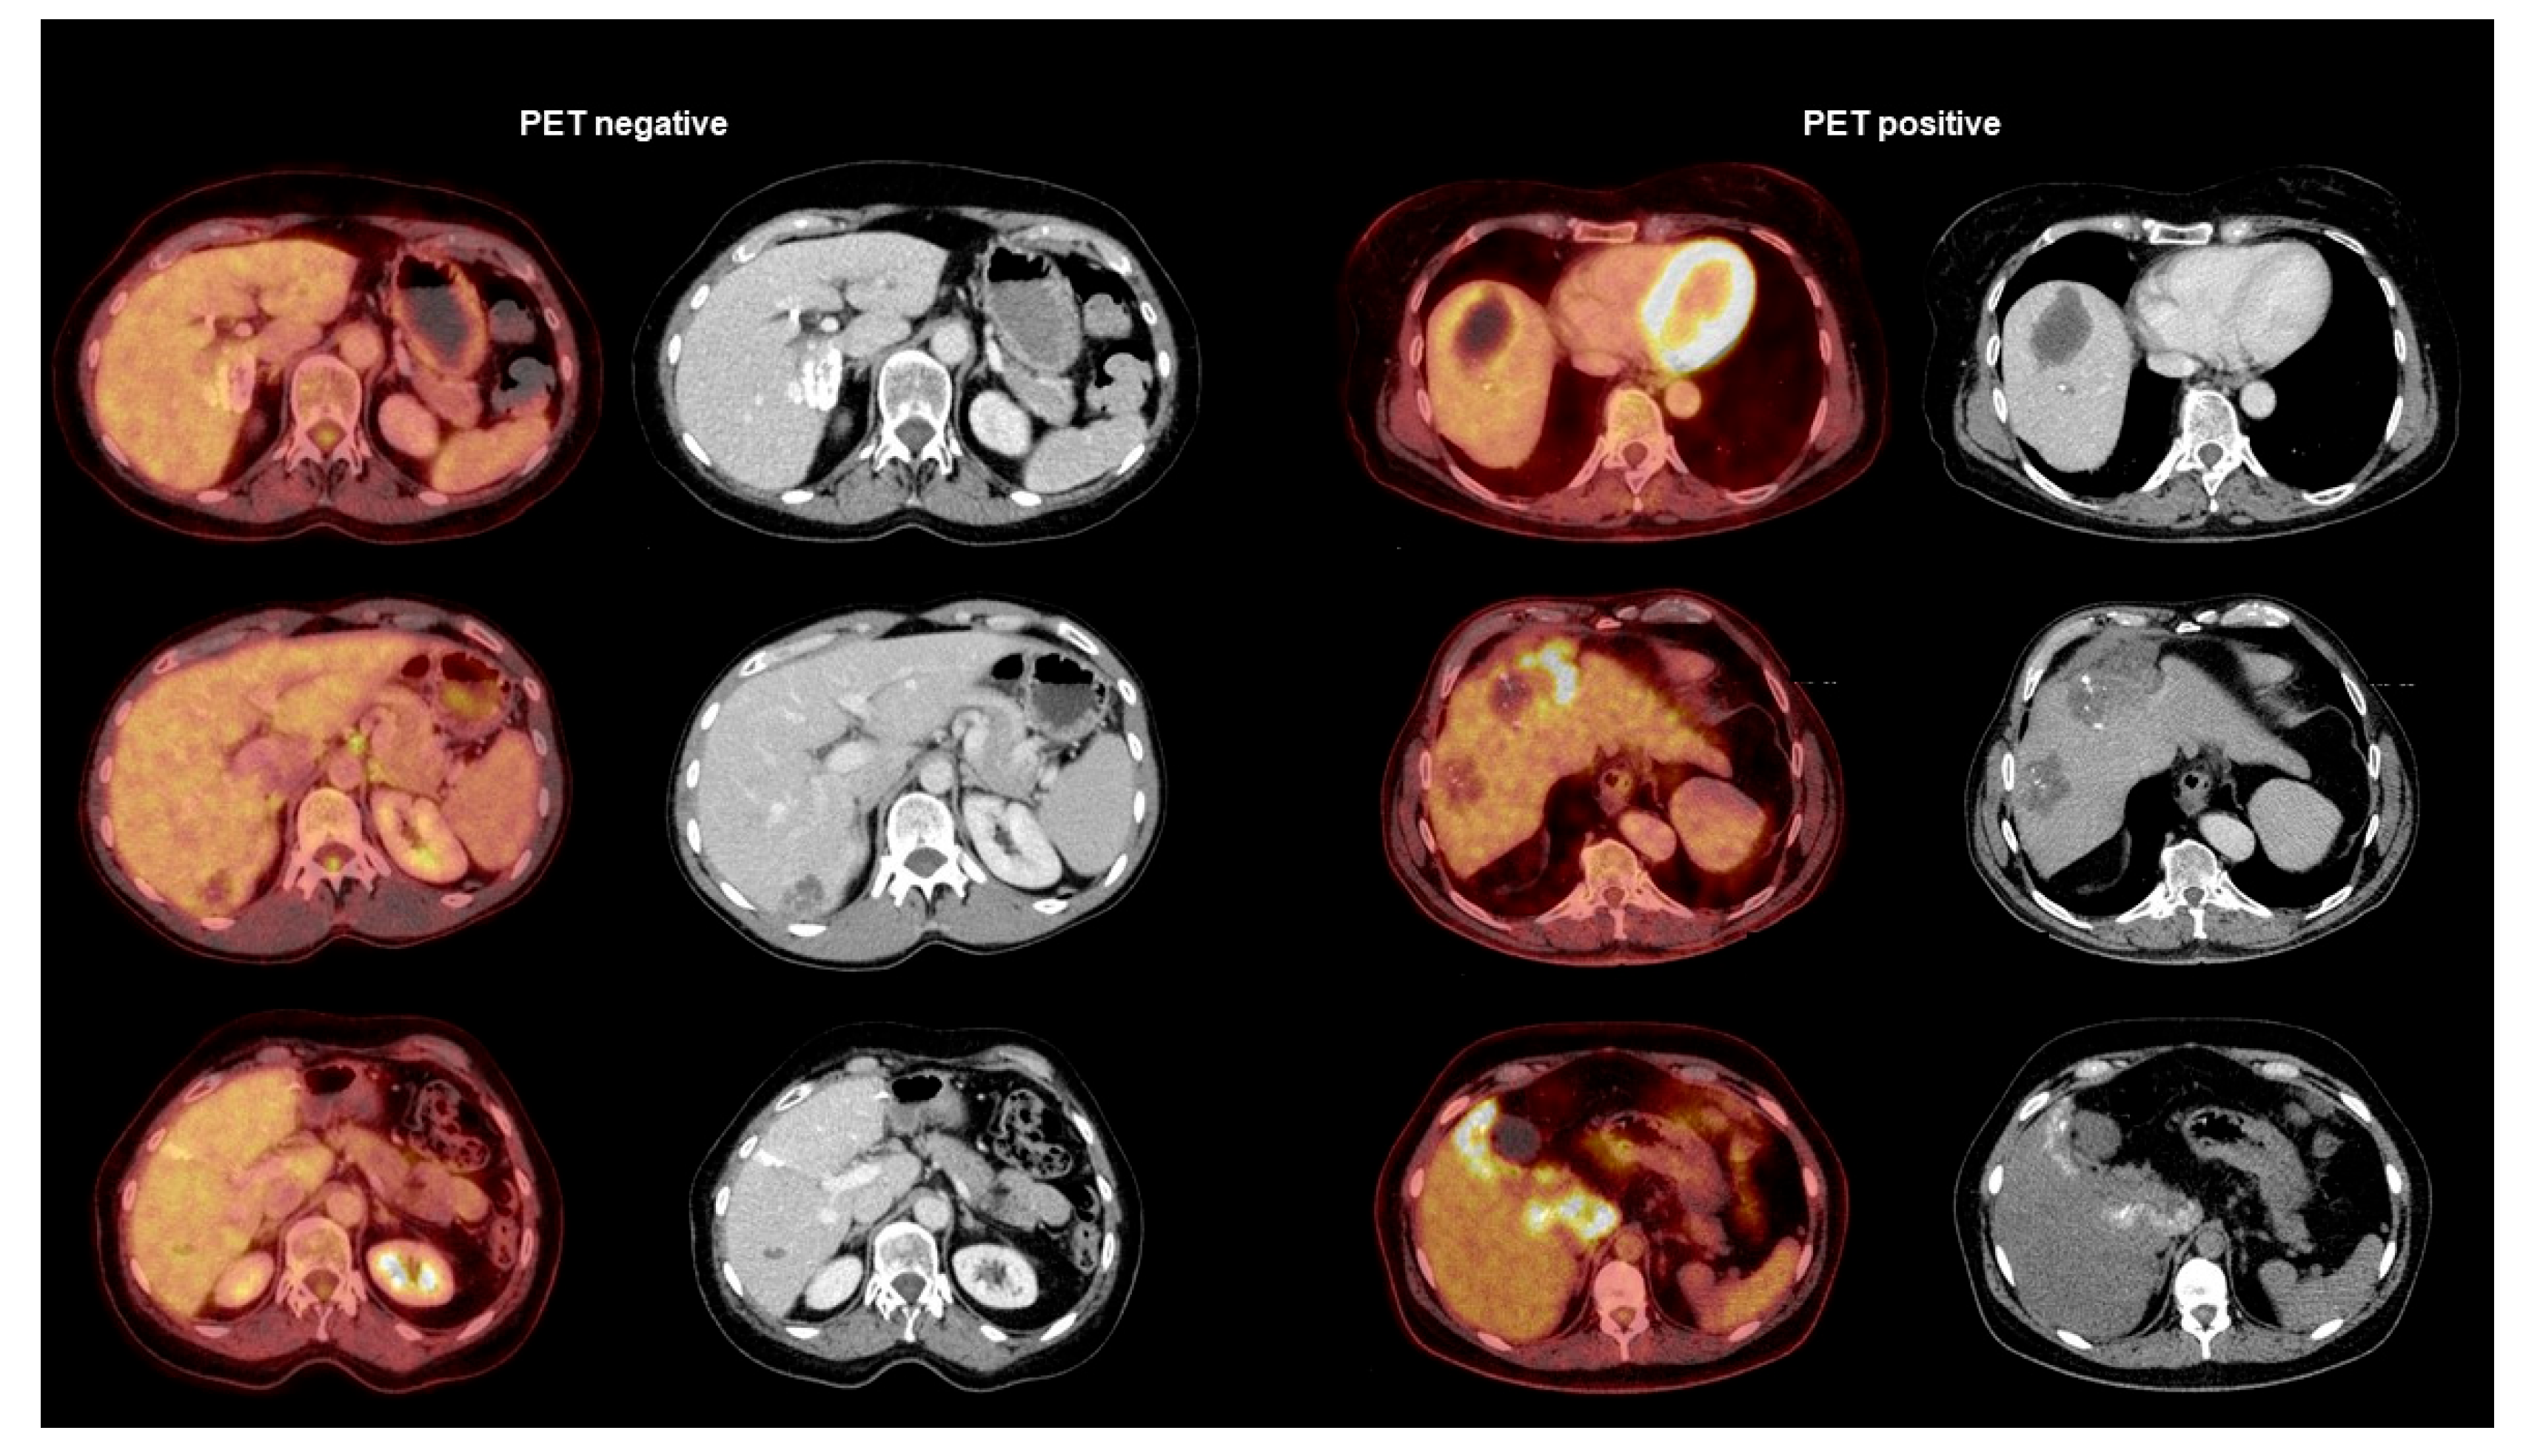

2.5. PET/CT Study

3.3. Biomarkers in Relation to PET/CT Results